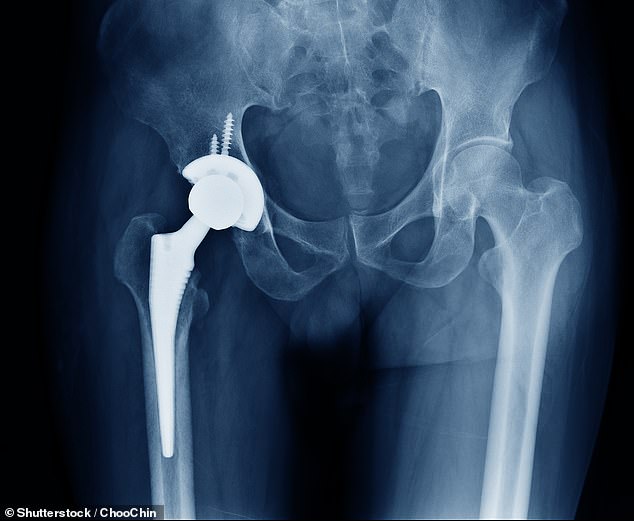

The cement acts as a high-strength grout, securing artificial joints to bone. In hip and knee replacements, it hardens rapidly to create a stable bond, ensuring implants remain firmly in place. Antibiotic-laced cements are crucial in revision cases, where infections or failed implants require temporary spacers or long-term re-fixation. Without these materials, hospitals may be forced to delay surgeries, leaving patients in chronic pain and reducing the chances of successful outcomes.